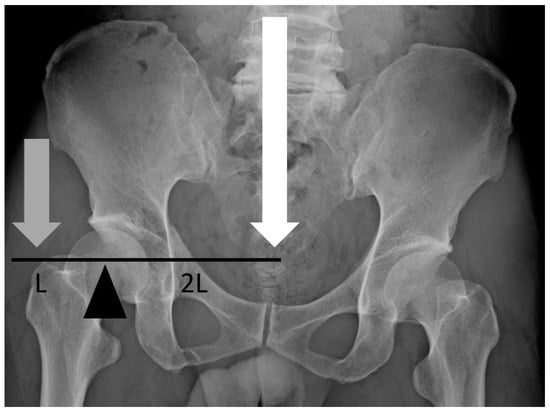

| Keshishyan et al., 1995 | Cross measurement method (Keshishyan Method) [14] | The measurement method described by Keshishyan et al. for assessing the displacement of pelvic ring continuity in children used only the AP pelvic view. Originally, this method was applied for skeletally immature patients and measures the distance from the inferior aspect of the sacroiliac (SI) joint to the contralateral triradiate cartilage. We used the modified method described by Lefaivre et al. to assess our adult patients. Observers were instructed to measure from the inferior SI joint (iliac side) to the inferior aspect of the teardrop in the AP pelvic view. “Y” was the length from the left SI joint to the right teardrop, and “X” was the opposite. Observers were instructed to measure the distance using the measuring software. We then calculated the ratio (X/Y) to standardize the baseline of comparison of the displacement (Figure 4). |